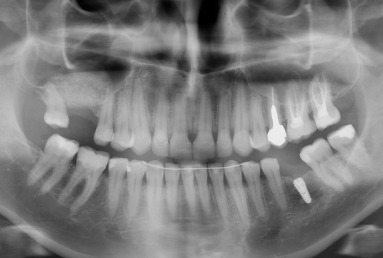

The final porcelain veneers for all frontal maxillary teeth are completed with tooth whitening and changing some composite fillings in lower frontals. On the lower left side a dental implant is inserted, on the upper right side external sinus lift is done. the treatment will be finalised with another upper implant, then two crowns on implants.